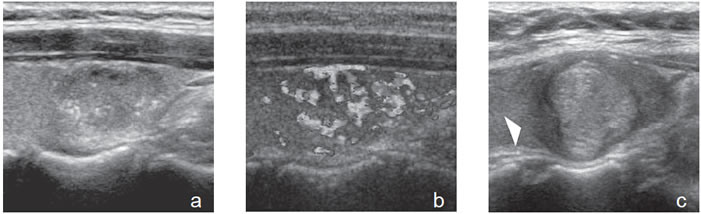

Las microcalcificaciones aparecen en la ecografía como focos ecogénicos puntiformes, sin sombra acústica y sin artefacto por reverberación, en el espesor del tejido sólido (Figura 8a). Desde el punto de vista histológico corresponden a conglomerados de cuerpos de psammoma, que son esférulas microscópicas laminarmente calcificadas. Se originan a partir de células necróticas, a menudo en las puntas de las papilas, que forman el nido sobre el cual se depositan las láminas de calcio. Se encuentran principalmente en carcinomas papilares (29% a 59%), pero pueden estar presentes en carcinomas medulares y anaplásticos11,16.

Las macrocalcificaciones aparecen como placas ecogénicas fragmentadas, o depósitos granulares amorfos que determinan sombra acústica hacia los planos profundos (Figura 8b). Patológicamente corresponden a calcificaciones distróficas secundarias a necrosis y fibrosis. La distribución puede ser central o periférica y ocurrir tanto en nódulos malignos como nódulos benignos de larga data. En el cáncer papilar pueden coexistir microcalcificaciones con calcificaciones gruesas, que se depositan en áreas de fibrosis y degeneración; las calcificaciones granulares centrales son el tipo más frecuente en el cáncer medular.

De todos los signos ecográficos asociados a malignidad, las microcalcificaciones es el más específico (85-95%). La presencia de microcalcificaciones en un nódulo predominantemente sólido aumenta el riesgo de cáncer en tres veces y la presencia de calcificaciones gruesas aumenta el riesgo de cáncer en dos veces. El valor predictivo de las microcalcificaciones varía entre 42% a 94% y la sensibilidad entre 26% a 59%5.

Un nódulo sólido, único, hipoecogénico, no encapsulado, con microcalcificaciones y vascularización intranodular corresponde con alta probabilidad a un carcinoma papilar (Figura 8). Este es un patrón clásico de malignidad y los signos pueden estar en diferentes proporciones o aparecer otros adicionales.

La mayoría de los cánceres papilares11,13 son hipoecogénicos (63%-90%) pero la hipoecogenicidad por sí sola no es un signo especifico, por lo que es importante que estén presentes otros hallazgos, especialmente microcalcificaciones (Figura 24). Las microcalcificaciones si están agrupadas pueden producir una sombra acústica y no deben confundirse con calcificaciones granulares gruesas (Figura 25).